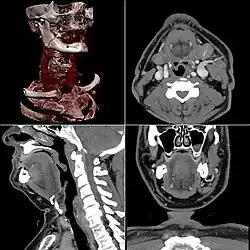

Neck

Contrast CT is generally the initial study of choice for neck masses in adults.[39] CT of the thyroid plays an important role in the evaluation of thyroid cancer.[40] CT scans often incidentally find thyroid abnormalities, and so is often the preferred investigation modality for thyroid abnormalities.[40]